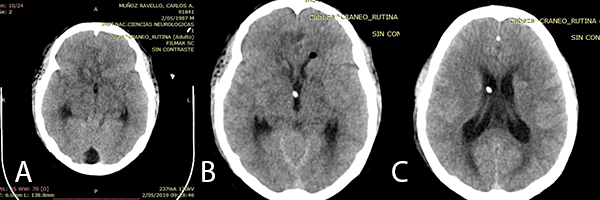

Imagen 1: RMN de cerebro: (A) y (B): cortes coronales en secuencia T1 con contraste donde se observan imágenes múltiples con captación de contraste en anillo. (C): corte axial en secuencia Flair que muestra edema peri lesional.

En el examen físico de ingreso, el paciente se encontraba en buen estado general, buen estado de hidratación, ventilando espontáneamente, Glasgow 15/15, pupilas isocóricas, fotorreactivas, sin déficit motor ni sensitivo, agudeza visual disminuida en ojo izquierdo. Inicialmente por la Resonancia Magnética (imagen 1), se sospechó de toxoplasmosis, recibiendo tratamiento médico, pero al no haber mejoría clínica es programado a biopsia por estereotaxia.

Las imágenes iniciales del paciente mostraron lesiones difusas. La secuencia T1 con contraste de la RMN mostró múltiples tuberculomas supra e infra tentoriales con un anillo que realza el contraste. Además en la secuencia Flair se evidenció edema perilesional de los tuberculomas. Sanei et al.(9) refieren que imagenológicamente la TBC en el SNC puede simular diferentes afecciones neurológicas (infecciosas y no infecciosas).